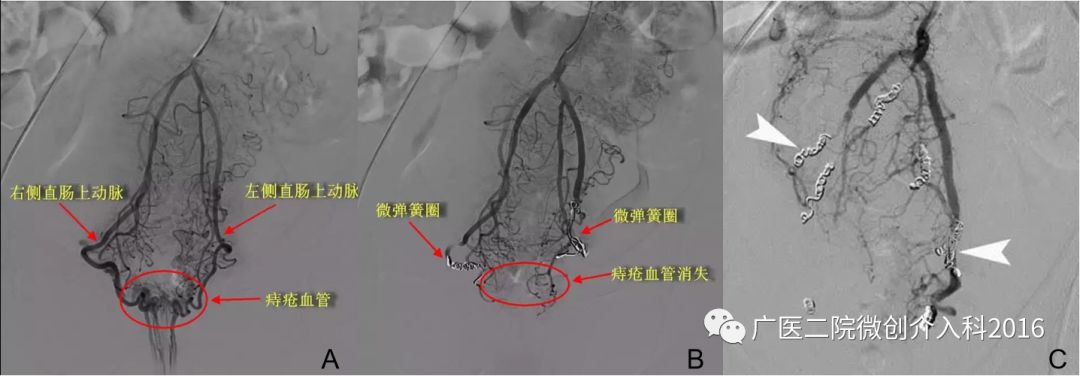

病例7:痔疮出血

患者诊断为痔疮出血,出血量大,药物止血治疗效果差、病情反复。图A行肠系膜下动脉和直肠上动脉造影,显示直肠区域痔疮血管丰富,明确诊断为痔疮出血。图B经微导管注入弹簧圈栓塞双侧直肠上动脉。图C再次造影原痔疮血管消失,患者痔疮出血停止。